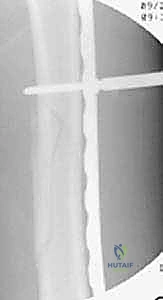

Intraoperative templating is a critical step before making any incisions. The contoured plate is placed on the skin over the anterior thigh. Using the fluoroscopic C-arm in a lateral projection, the surgeon "shadows" the plate against the lateral femur. This allows for real-time visual confirmation that the length is appropriate (spanning from the trochanteric apophysis to the distal metaphysis) and that the contour closely matches the native femoral bow.

TECH FIG 2 • The plate on the anterior thigh shadowing the lateral femur with fluoroscopy to evaluate plate contour and length.

Clinical & Radiographic Imaging Archive